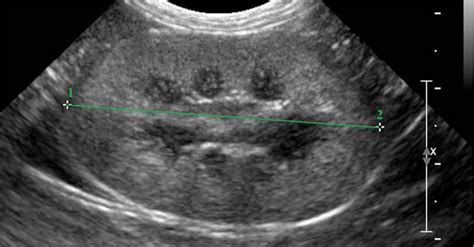

Būtini ultragarso tyrimai pagal Lietuvos Respublikos sveikatos apsaugos ministro įsakymą, atliekami du kartus: 11-14 ir 18-20 nėštumo savaitę. Šie tyrimai atliekami per pilvo sienelę, dažniausiai įprastiniu 2D echoskopu. Jų metu vertinama placenta, vaisiaus dydis ir būklė, stebimi judesiai ir vandenų kiekis. Šiuo laiku tiksliausiai pasakoma, ar nėra apsigimimų, ar vidaus organų struktūra normali, bei nustatoma vaisiaus lytis.

Antrosios echoskopijos, atliekamos 18-20 nėštumo savaitę, metu nustatoma daugiau kaip 50 proc. vaisiaus padėties gimdoje. 3D / 4D echoskopu 18-20 nėštumo savaitę galima matyti, kaip vaisius spardosi - jis jau gali vartytis, judinti kojytes, rankytes, pirštukais liesti veidą, juos čiulpti. Vaikelio veiduko nuotraukos 3D ultragarso tyrimu yra aiškiai matomos nėštumo pabaigoje (26-32 sav.).

Vaisiaus vystymasis ir nėštumo trukmė kartais gali nesutapti su echoskopijos duomenimis, palyginti su paskutinių menstruacijų data. Nėštumo laikas, remiantis vaisiaus biometrijos duomenimis, nustatomas tiksliausiai 18-20-ąją savaitę. Tačiau, kaip rodo kai kurių moterų patirtys, gali pasitaikyti ir ankstesnių nesutapimų. Pavyzdžiui, viena moteris pastebėjo, kad pagal mm turėjo būti 9 savaitės, o echo rodė 7 savaitės. Kitos mamos dalijasi panašiomis patirtimis, kai pradžioje vaisius rodėsi esantis 2 savaitėmis mažesnis, o vėliau - didesnis savaite. Svarbu atkreipti dėmesį, kad tiksliausias yra pirmasis echoskopijos tyrimas iki 12 savaičių - pagal jį gimdymo terminas nustatomas tiksliausiai.

Kartais nėštumo trukmė, nustatyta pagal echoskopiją, gali skirtis nuo tos, kurią moteris pati sau paskaičiuoja nuo pirmos vaisingosios dienos. Tai gali būti susiję su individualiais ciklo ypatumais, pavyzdžiui, ilgesniu nei 28 dienų ciklu. Dėl šių priežasčių gydytojai echoskopijos metu atlieka vaisiaus biometriją, matuodami skirtingus parametrus, tokius kaip:

- BPD (diameter biparietalis) - tarpmomeninis matmuo;

- FO (diameter frontooccipitalis) - pakaušio-kaktos matmuo;

- HC (head circumference) - galvos apimtis;

- ABD (diameter abdominalis) - pilvo matmuo;

- AC (abdomen circumference) - pilvo apimtis;

- Fe (femur) - šlaunikaulio ilgis.

Remiantis šiais matmenimis, apskaičiuojamas vaisiaus svoris ir tiksliau nustatomas nėštumo laikas.